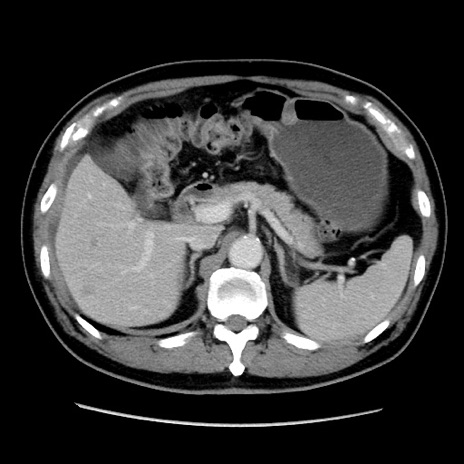

症例16(横断像)

【症例】 70歳代男性

【主訴】 腹痛、嘔吐

【現病歴】 約1ヶ月前より間欠的に腹痛と嘔吐あり、当院消化器内科を受診したところCTで多発する肝臓のLDAを指摘され、精査中であった。以降は消化器症状は安定していたが、2日前より嘔気と腹痛があり、同日より排便・排ガスが消失した。改善認めず、 本日、救急外来を受診した。

【既往歴】 大腸ポリープ切除後。

【身体所見】意識清明・会話良好、BT 36.3℃、BP 127/80mmHg、 P 80bpm、腹部:膨満あり、平坦・軟、上腹部正中および下腹部正中に圧痛あり、反跳痛なし、筋性防御なし。

【データ】WBC 7200、CRP 0.77